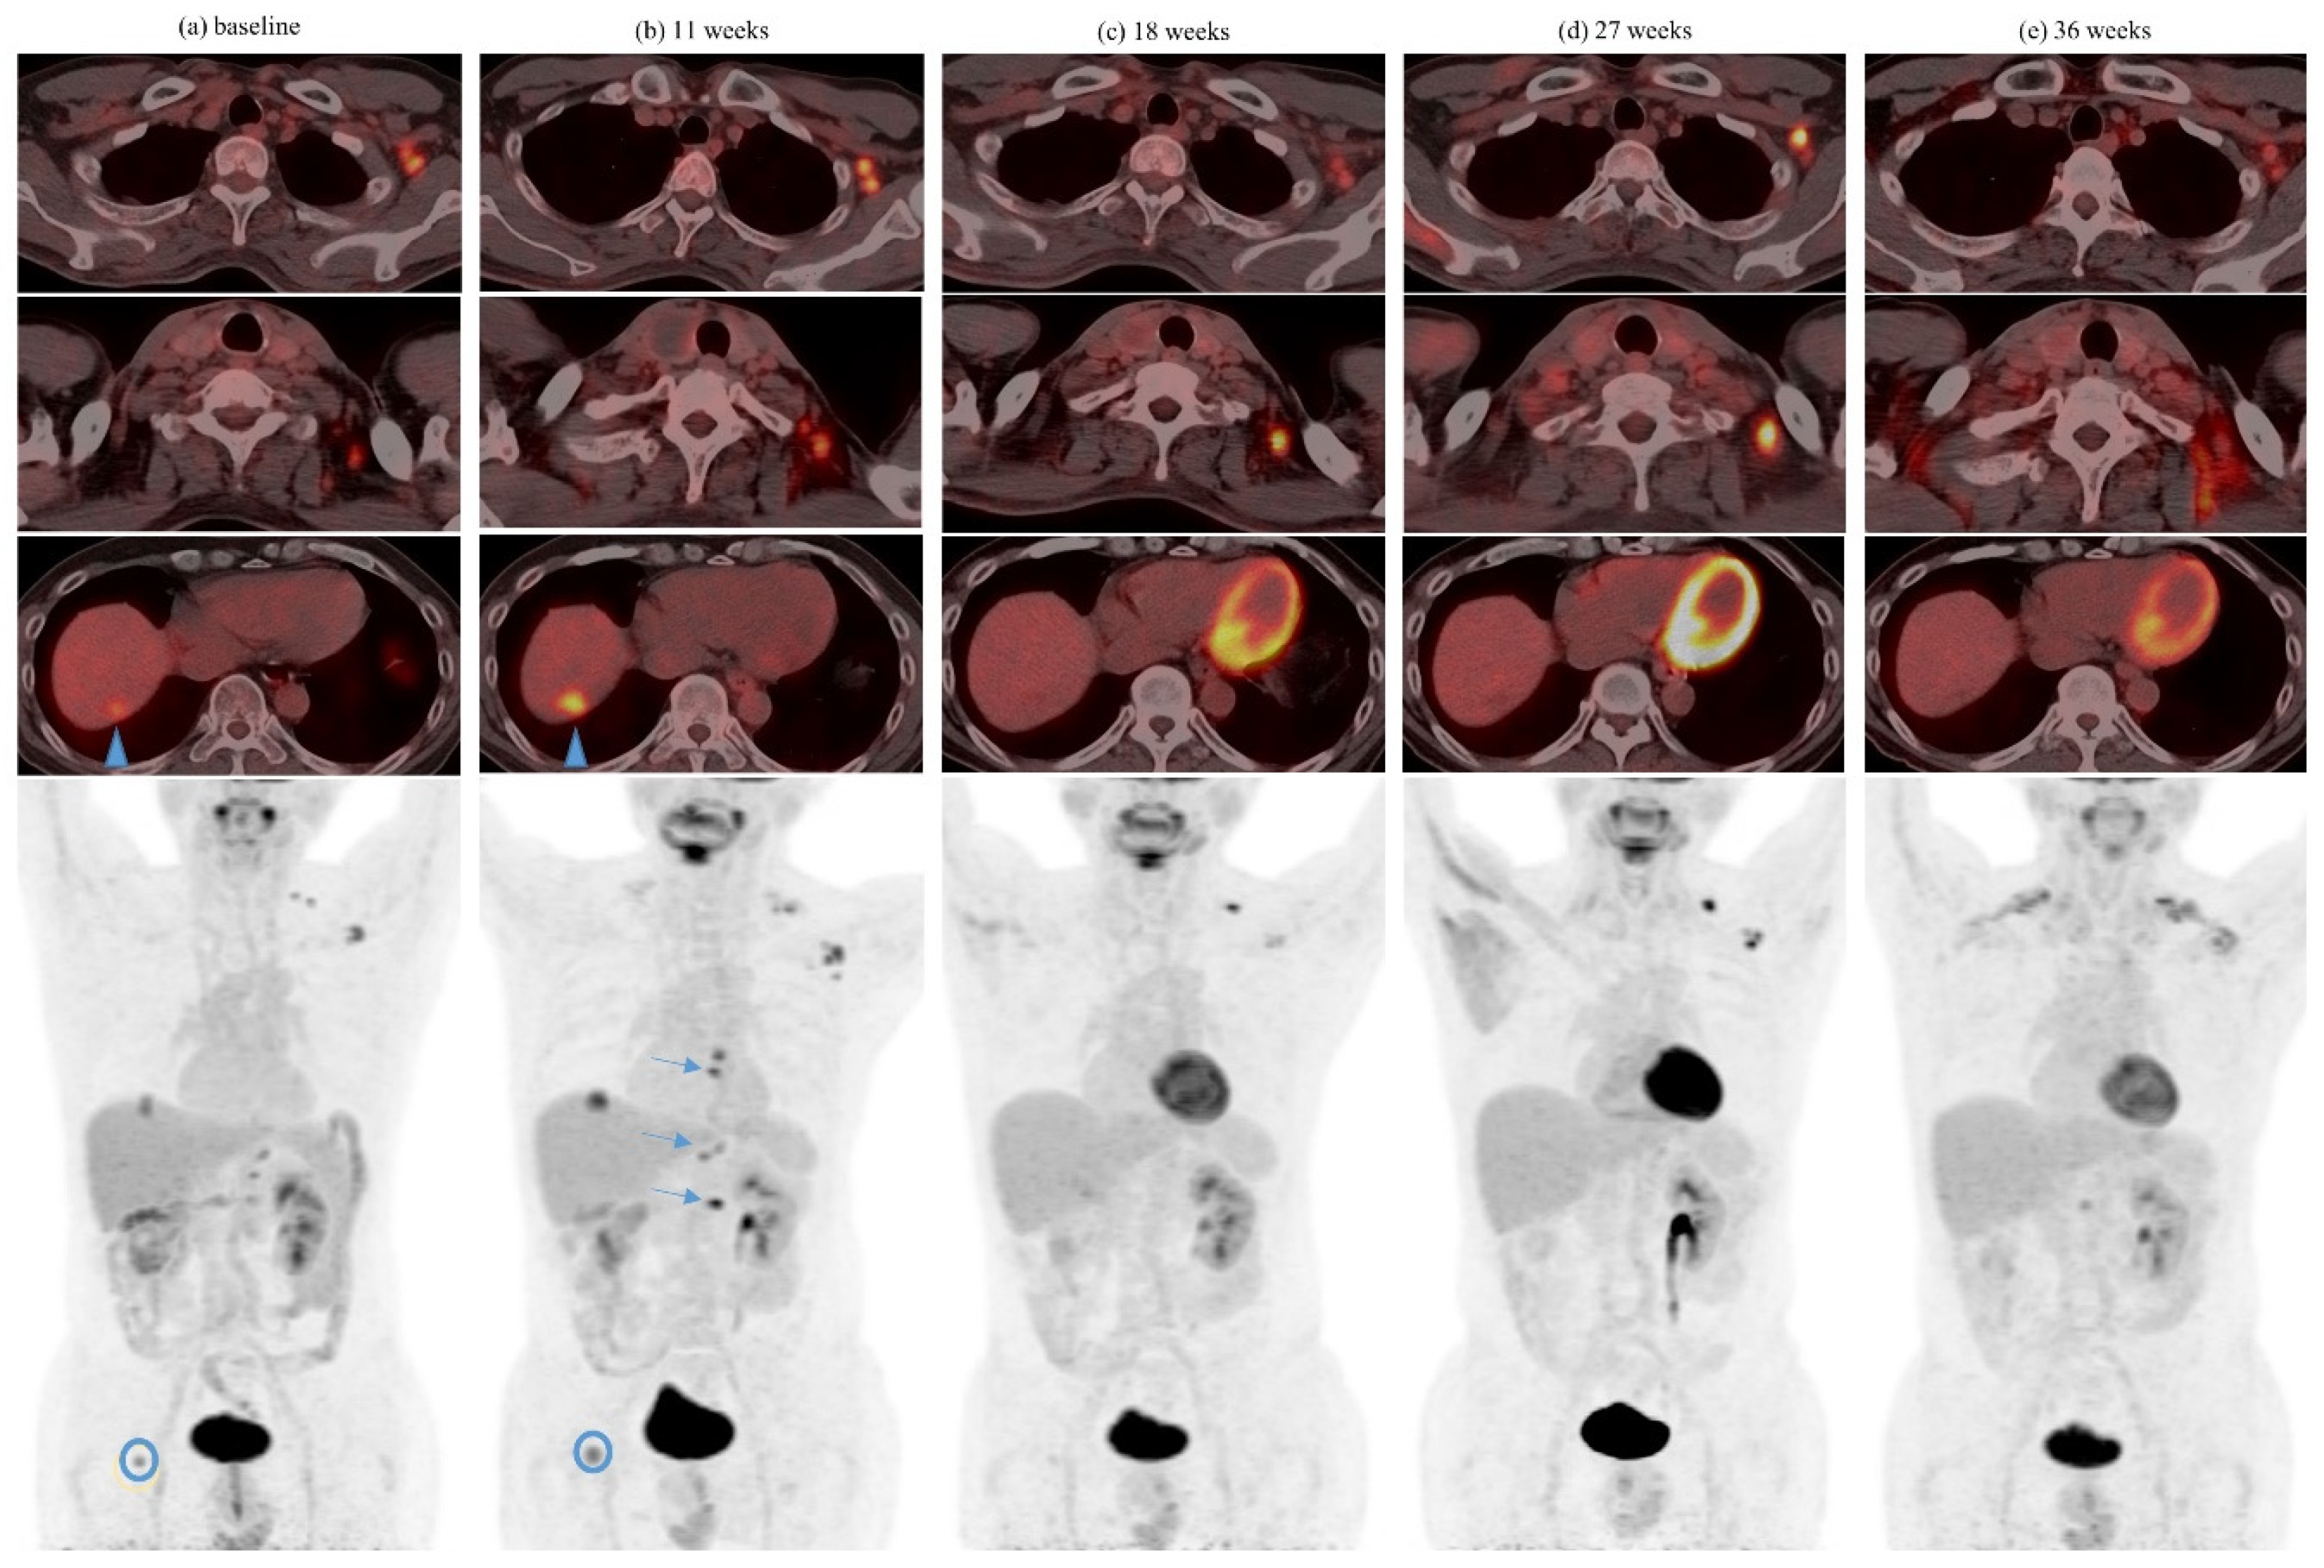

| 3 | Ipilimumab + Nivolumab | 10 14 | 36Gy/3 30Gy/5 | Yes Yes | Lung Adrenal | Lung, 2 Lung, 1 | 2 5 | 1 tumor with abscopal response after initial enlargement post SBRT 4 |

| 4 | Ipilimumab + Nivolumab | 12 | GKS 5 25Gy | 1 month after last dose of ICI | Brain (4 lesions) | Intramuscular, 1 | 2 | |

| 5 | Pembrolizumab | 3 6 | 8Gy/1 27Gy/3 | Yes Yes | Femur Pubic bone | Liver, several | 1 | Concurrent axitinib from prior line of treatment maintained |

| 6 | Nivolumab | 17 26 | 54Gy/3 42Gy/5 25Gy/5 | Yes Yes | Lung Lung | Lung, 2 Lung, 2 | 5 3 | Prior spontaneous regression and dissociated response after cytoreductive nephrectomy |